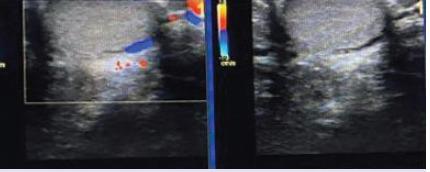

伴有睾丸外精索静脉曲张病例的睾丸内精索静脉曲张的区域分布。

Regional distribution of intratesticular varicoceles accompanying extratesticular varicocele cases.

Approximately 10,537 patients with scrotal pain and swelling who visited our hospital between August 2014 and May 2020 and underwent scrotal colour Doppler ultrasonography were included in this study. Of these patients, 2285 had ETV, and the remaining patients (n=8252) had other testicular pathologies such as acute-chronic torsion, testicular mass, orchitis, significant testicular atrophy, or isolated extratesticular varicocele, and were thus excluded from the study. Among the 2285 patients, only 20 had ITV.

Of the 20 patients with ITV, 2 had isolated ITV, and the remaining had ITV accompanying ETV, of whom only one had a right ETV. One patient had left testicular atrophy accompanying an isolated ITV. Among the ITV cases, subcapsular ITV was the most common (n=13), followed by central ITV (n=4) and subcapsular and hilar ITV (n=3). The patients' ages ranged from 18 to 30 years.

在20例ITV患者中,2例为孤立性ITV,其余患者为ITV伴发ETV,其中只有1例为右侧ETV。1例患者伴有孤立性ITV的左侧睾丸萎缩。在ITV病例中,最常见的是包膜下ITV(n = 13),其次是中央ITV(n = 4)和包膜下及肾门ITV(n = 3)。患者年龄在18至30岁之间。